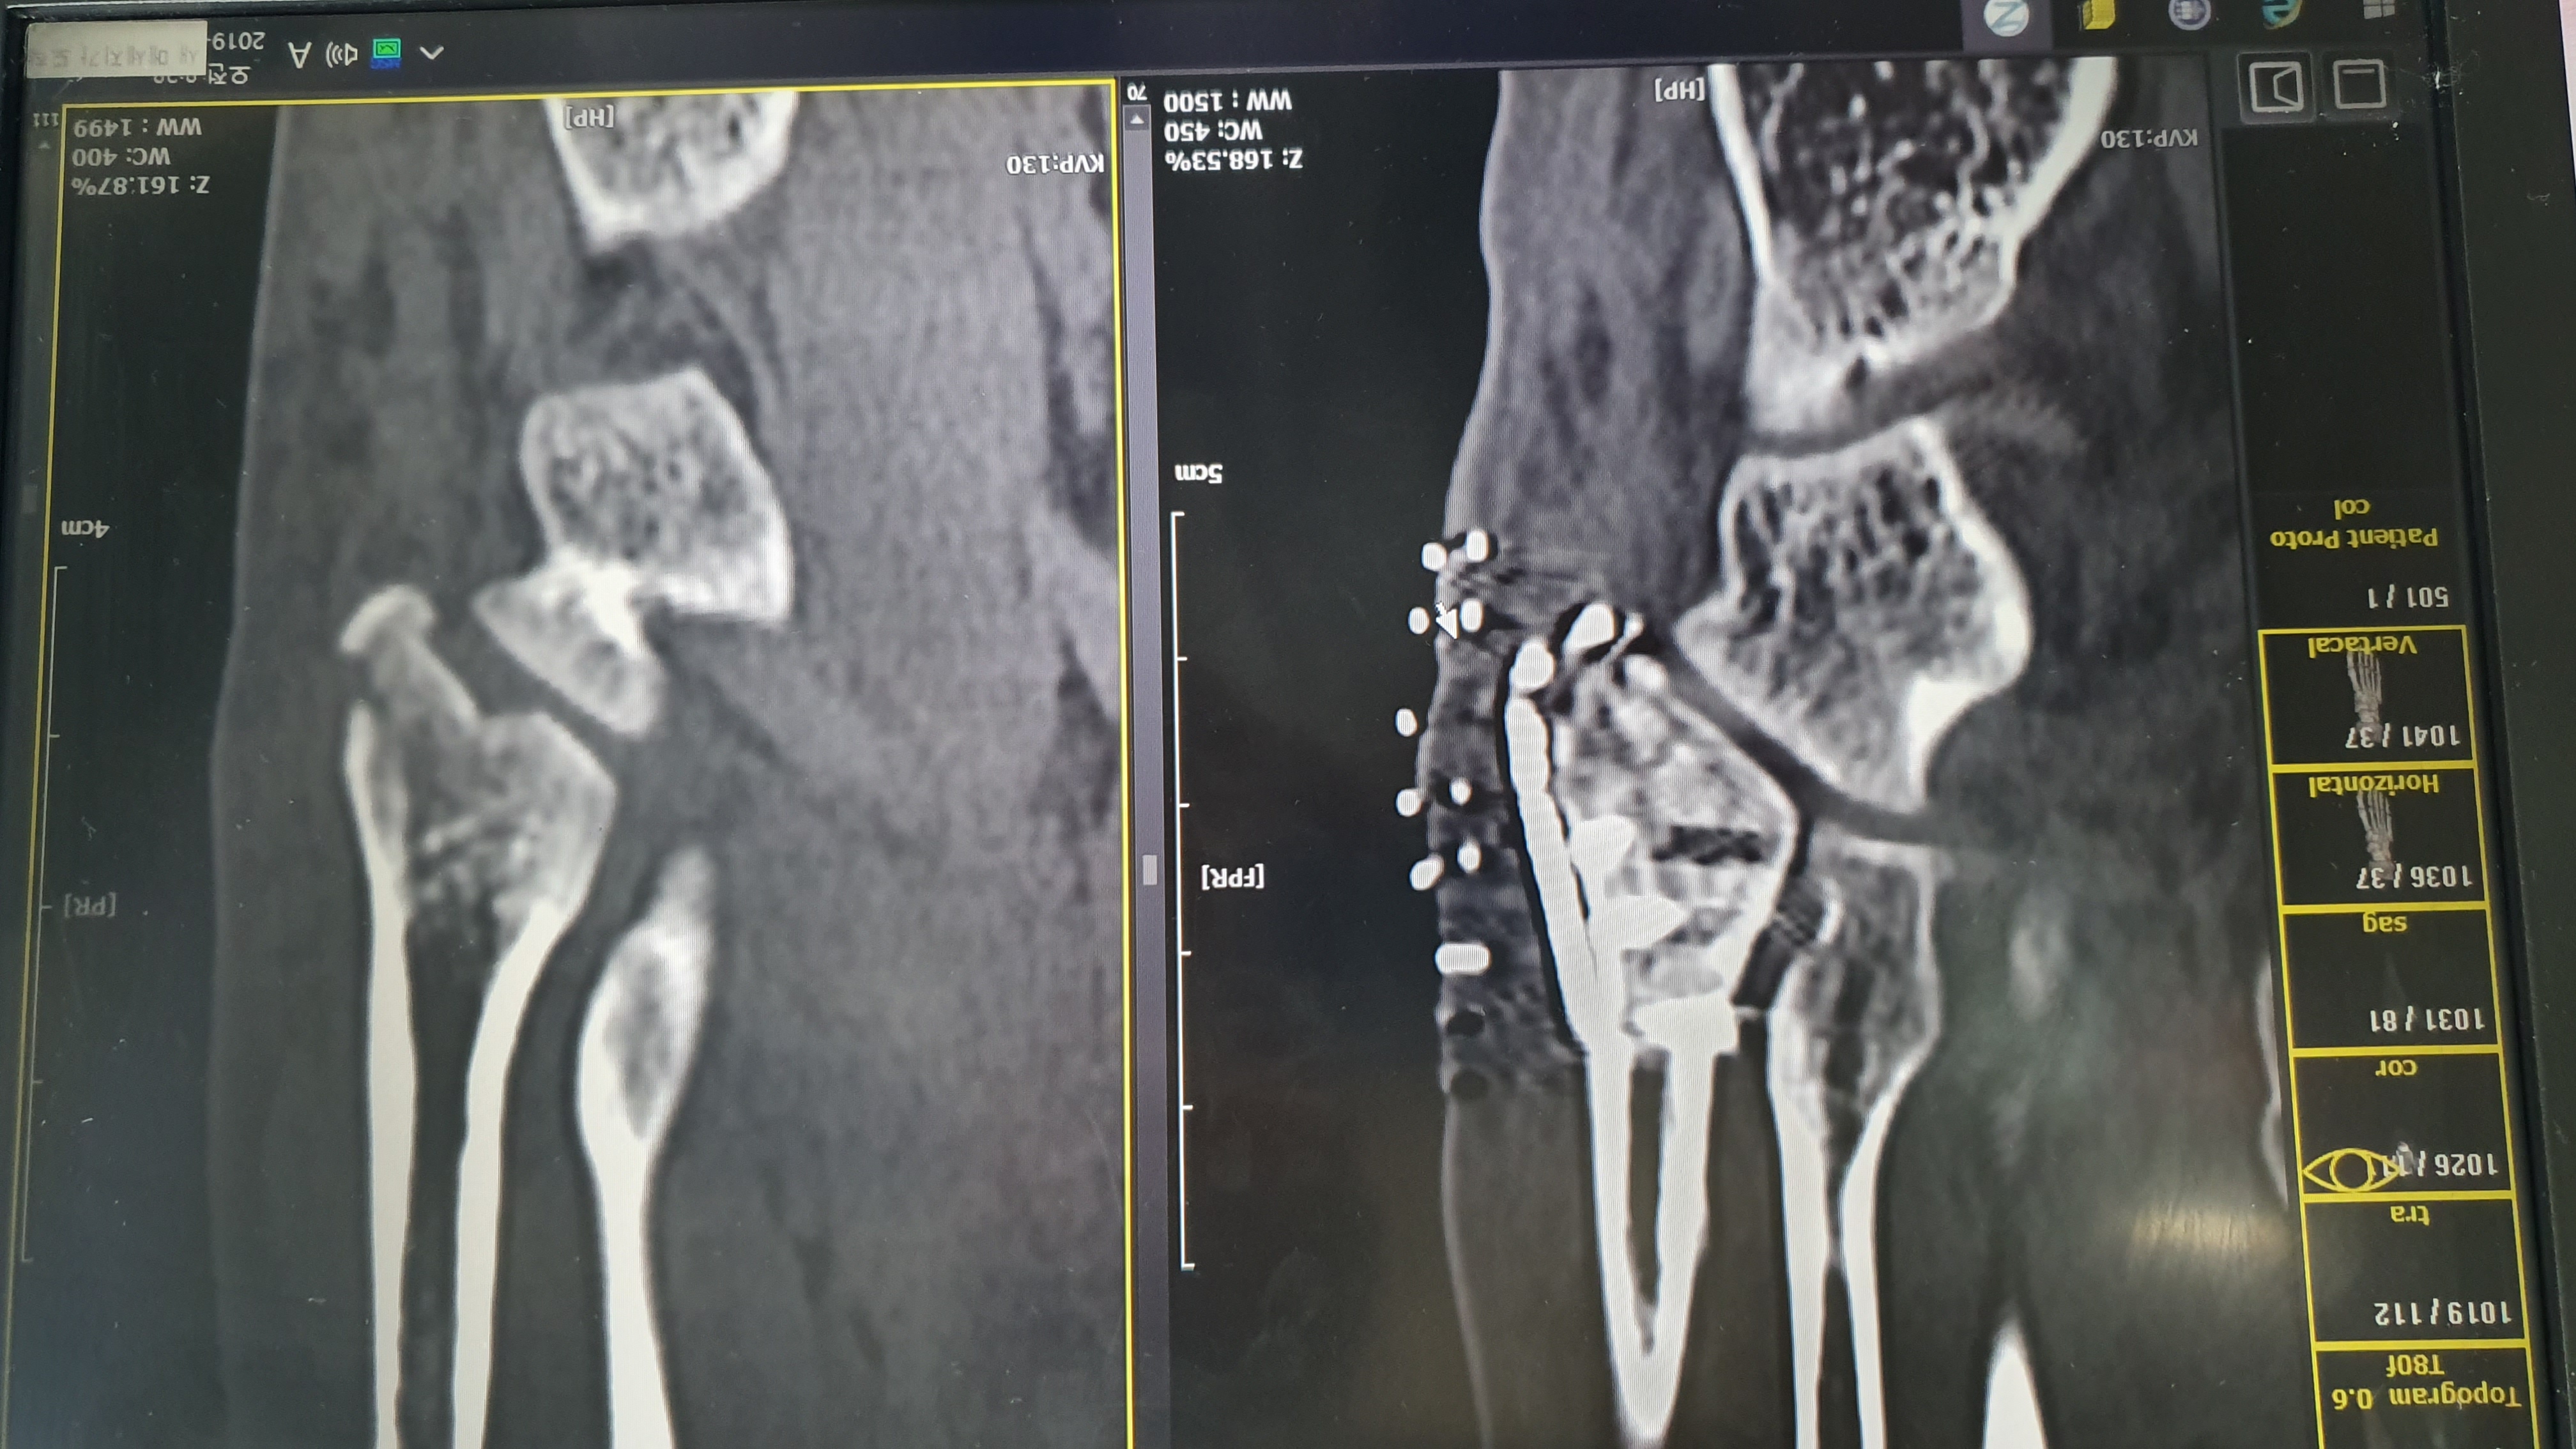

새끼발가락과 이어지는 5번 중족골에 몸무게 전체가 실리며..

똑 하고 부러져 핀을 박은 상태입니다.